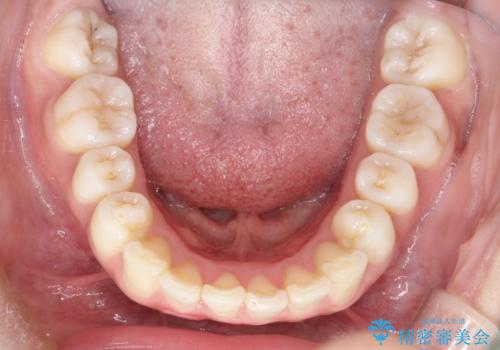

上下の前歯の距離が近くなり、前歯で咬みやすくなり、審美的にも改善できました。

- 上の前歯が出てて、前歯で咬めないとのことで来院されました。

上顎の歯を1本抜歯して、前歯のガタガタと、前方に出ているのを改善する計画としました。